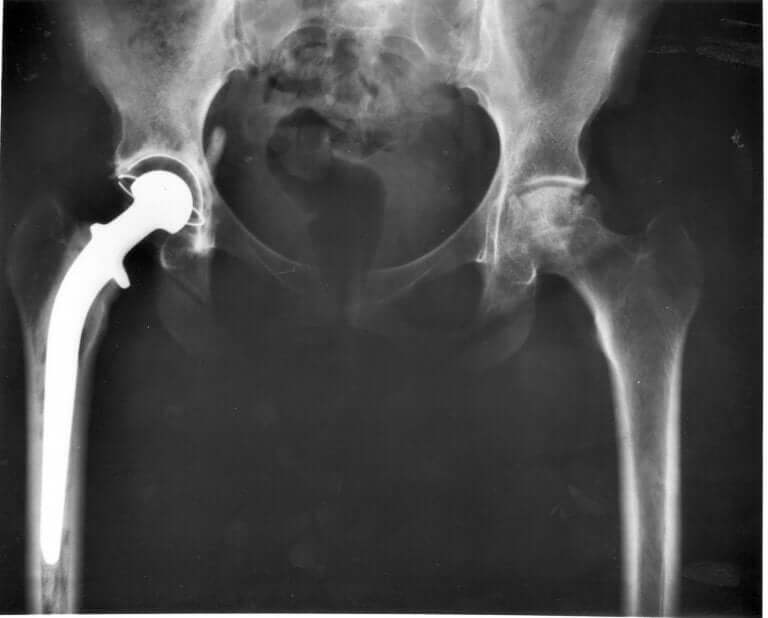

Your vet will have to look at your cat’s hip joints and take pelvic X-rays to identify the exact problem. If your cat does, in fact, have hip dysplasia, there are some treatments out there to give it relief and slow down the symptoms. Unfortunately, there’s still no cure.

Some of those treatments involve things like physical therapy, restricting certain activities, anti-inflammatory medication (oral or injected), and weight watching. In more serious cases, it may need hip replacement surgery.